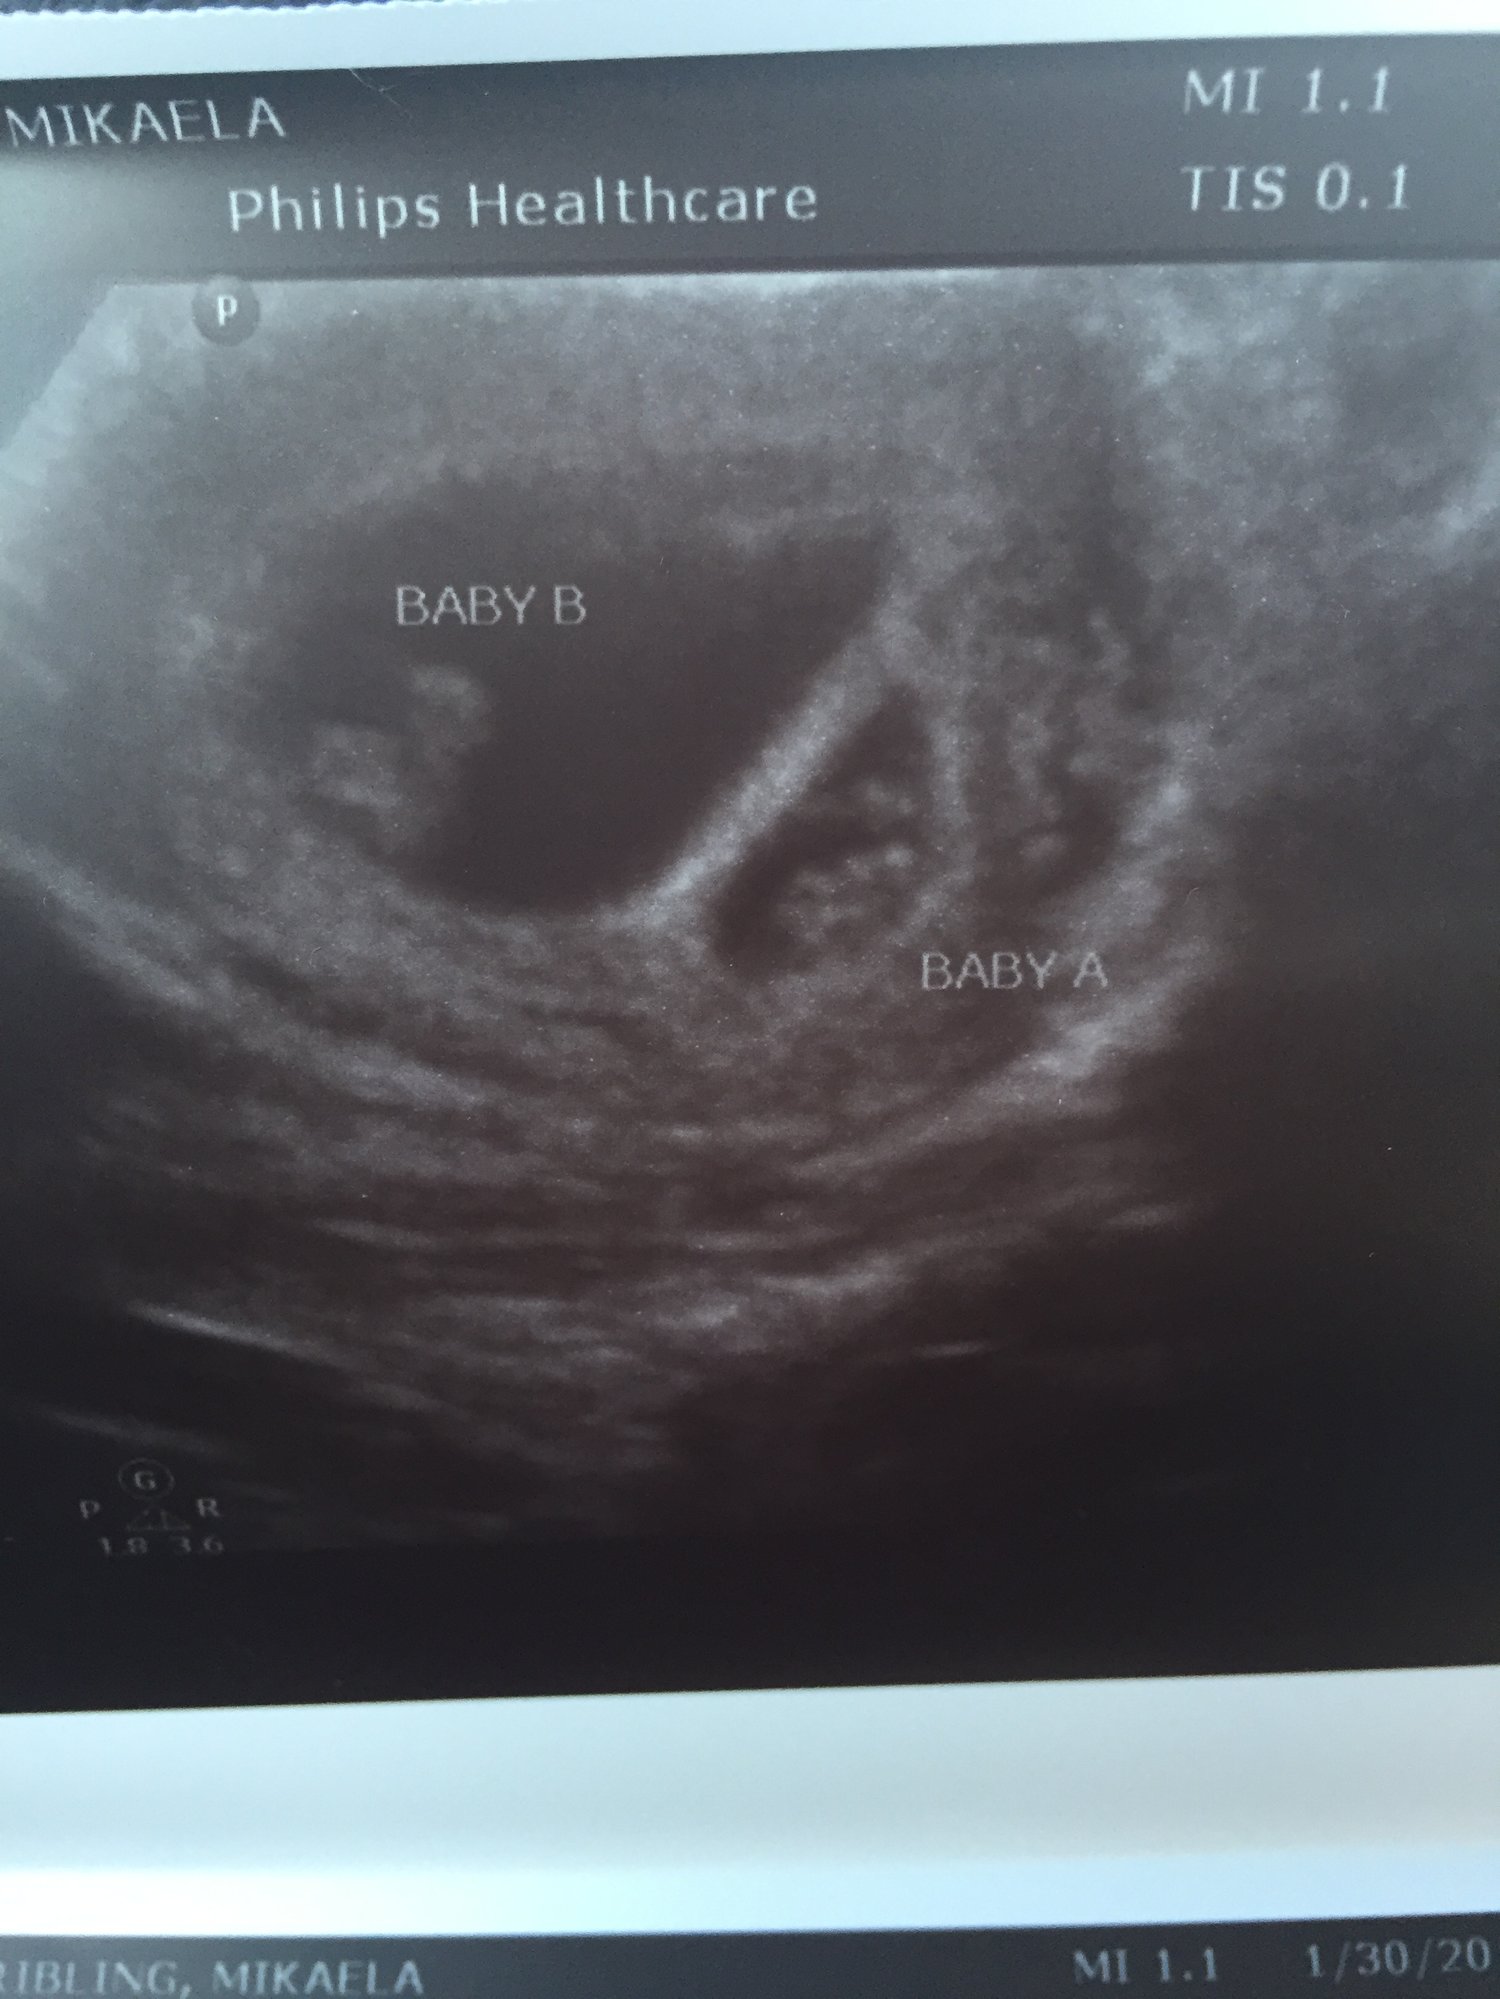

• @xxkberxx congrats so glad I got some twin mama counterparts!